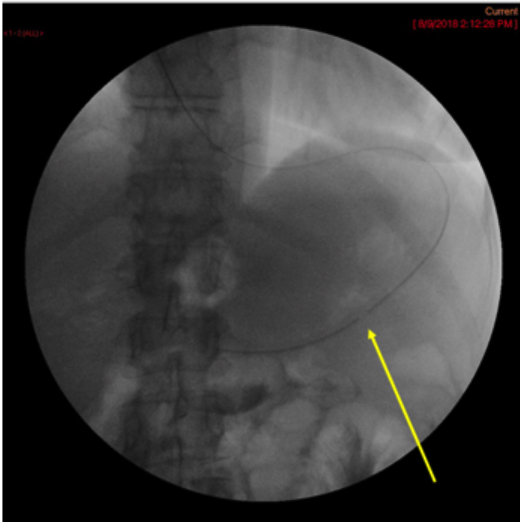

- Ensure that the most proximal side hole is inside the gastric body and obtain a spot film demonstrating the tube in the correct position

(key image 1).

- The most proximal side hole is indicated by a break in the radiopaque stripe on the tube.

- In the image above, it is indicated by the yellow arrow.